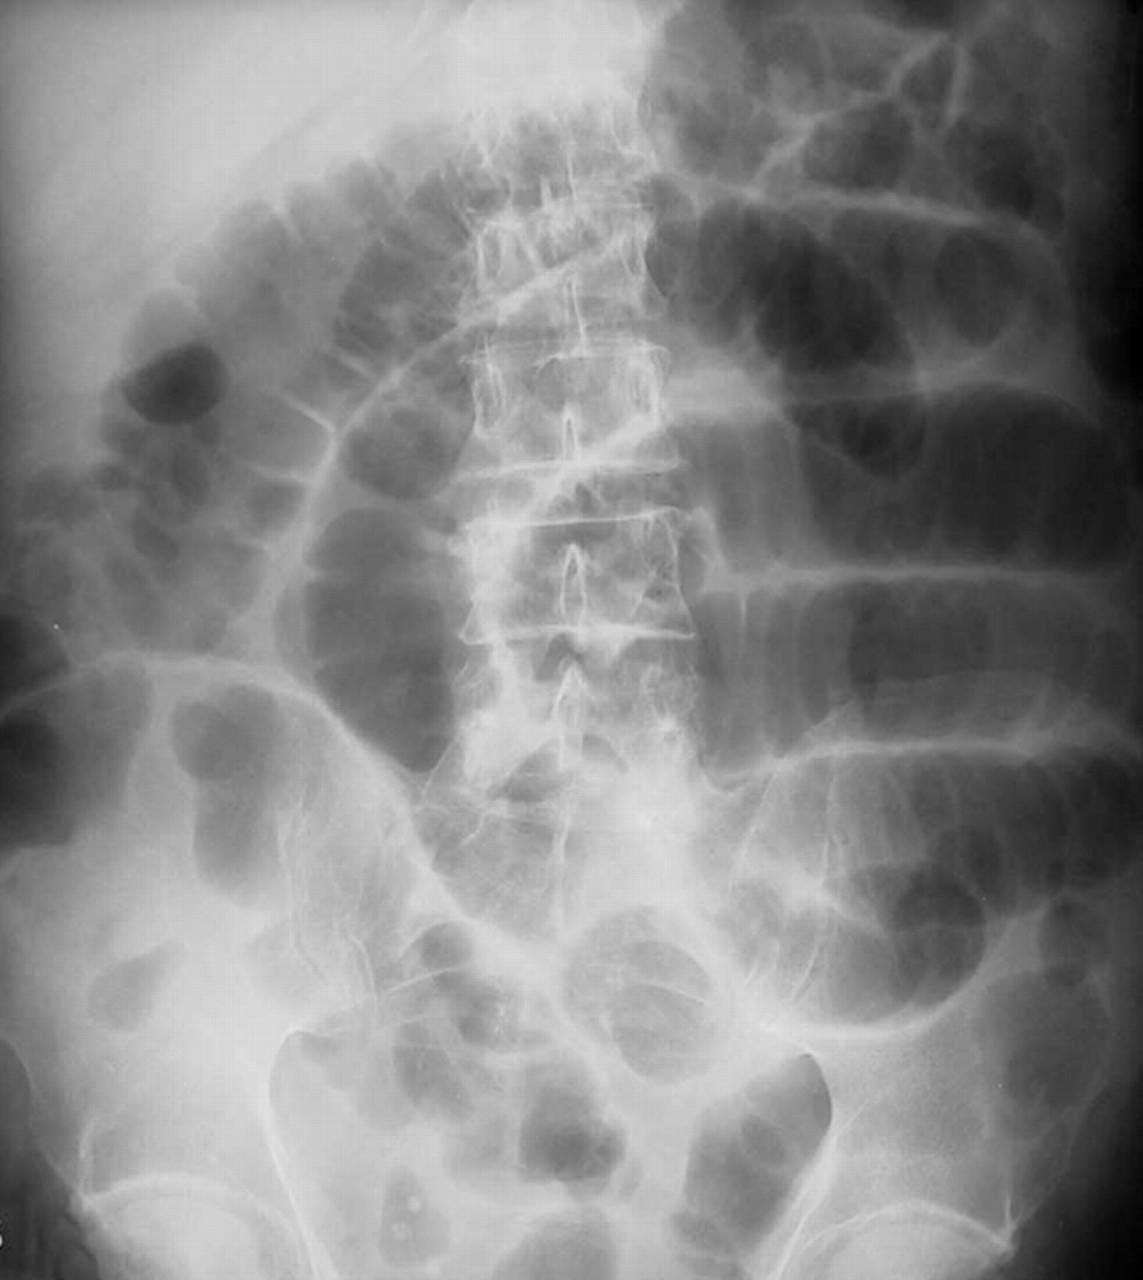

Боль при кишечной непроходимости, как правило, является схваткообразной и очень выраженной. Во время приступа боли пациент стремится занять вынужденное положение (обычно, коленно-локтевое или на корточках), у него отмечаются некоторые симптомы болевого шока (побледнение кожи, тахикардия, понижение давления и холодный пот). При высокой кишечной непроходимости (непроходимости тонкого кишечника) возникает частая рвота. В некоторых случаях возможно наличие кишечного содержимого в рвоте. Также при илеусе возникает заметная асимметрия живота.

Дифференциальная диагностика кишечной непроходимости проводится с прободной язвой двенадцатиперстной кишки и желудка, острым панкреатитом, холециститом, острым аппендицитом, почечной коликой и внематочной беременностью.